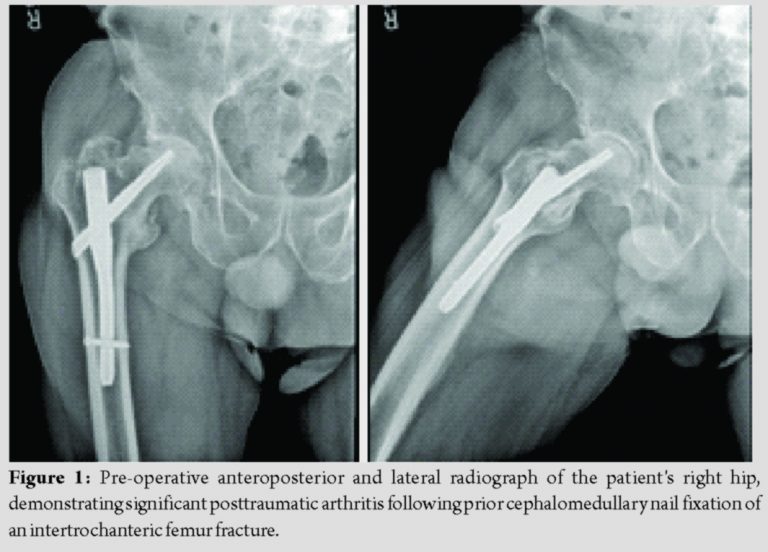

A 71-year-old man with a history of FXI deficiency presented to the orthopedic clinic with complaints of progressively worsening pain in his right hip. Of note, the patient had previously undergone cephalomedullary nail fixation of a right proximal femur fracture 3 years prior by another local orthopedic surgeon. The patient subsequently went onto heal this fracture; however, he did develop severe degenerative changes in his right hip along with significant post-traumatic arthritis (Fig. 1). Surgical options along with their risks and benefits were reviewed with the patient who ultimately elected to undergo conversion THA. Of note, the patient had a history of significant post-operative bleeding following a right-sided hernia repair done 19 years prior. At that time, his FXI deficiency was treated with only a single dose of fresh frozen plasma (FFP). Since then, he had undergone cephalomedullary nail fixation of both his left and right hips 3 and 5 years prior, respectively. He did not experience any post-operative bleeding or thromboembolic complications following either hip fracture surgery. The patient’s hematologist devised the following perioperative management strategy before his first hip fracture surgery: Preoperatively, a 5-g IV bolus of aminocaproic acid would be administered followed by aminocaproic acid as continuous venous infusion of 5 g in a 250 mL solution at 50 mL/h throughout the perioperative period. Postoperatively, tranexamic acid (TXA) would be administered as a 1 g bolus followed by 1 g every 8 h for 72 h for a total of nine doses. The patient would then be discharged on oral TXA at 1300 mg every 8 h for the first 7 days, with the frequency decreased to every 12 h for the subsequent week. He would also be administered subcutaneous enoxaparin 40 mg daily for venous thromboembolism prophylaxis.

Before conversion THA surgery, the patient was seen in the hematology clinic so that his perioperative plan could be reviewed before this surgery. The patient had been previously seen in this clinic at the time of this right hip fracture. At that time, the patient’s FXI deficiency was confirmed, with his factor XI assay at 1.9%, well below the normal value of 50–150% activity. Given the patient’s success with the aforementioned hematologic plan, it was agreed that the same protocol would be used for his THA conversion surgery. The patient was taken to the operating room for removal of the cephalomedullary nail and subsequent conversion to a THA. Pre-operative hemoglobin and hematocrit were 12.4 g/dL and 35.6%, respectively. Using the previous surgical incision, removal of the cephalomedullary nail was completed with some difficulty as the distal locking screw was stripped at the time of removal. Once this was completed, attention was turned to completing the THA. Utilizing a standard anterior approach, the proximal femur was cut in appropriate position, the acetabulum was reamed up to a size 57, and a size 58 cup was press-fit with excellent purchase. The cup was fixed with two screws into the ilium. Next, the femur was prepared. An 8″, size 18 Solution (Depuy, Warsaw Indiana) stem with a 36 + 5 head was deemed to provide adequate stability, and the final components were implanted. Blood loss was estimated at 700 mL. The patient was made toe-touch weight-bearing to the right lower extremity. There were no intraoperative complications experienced.